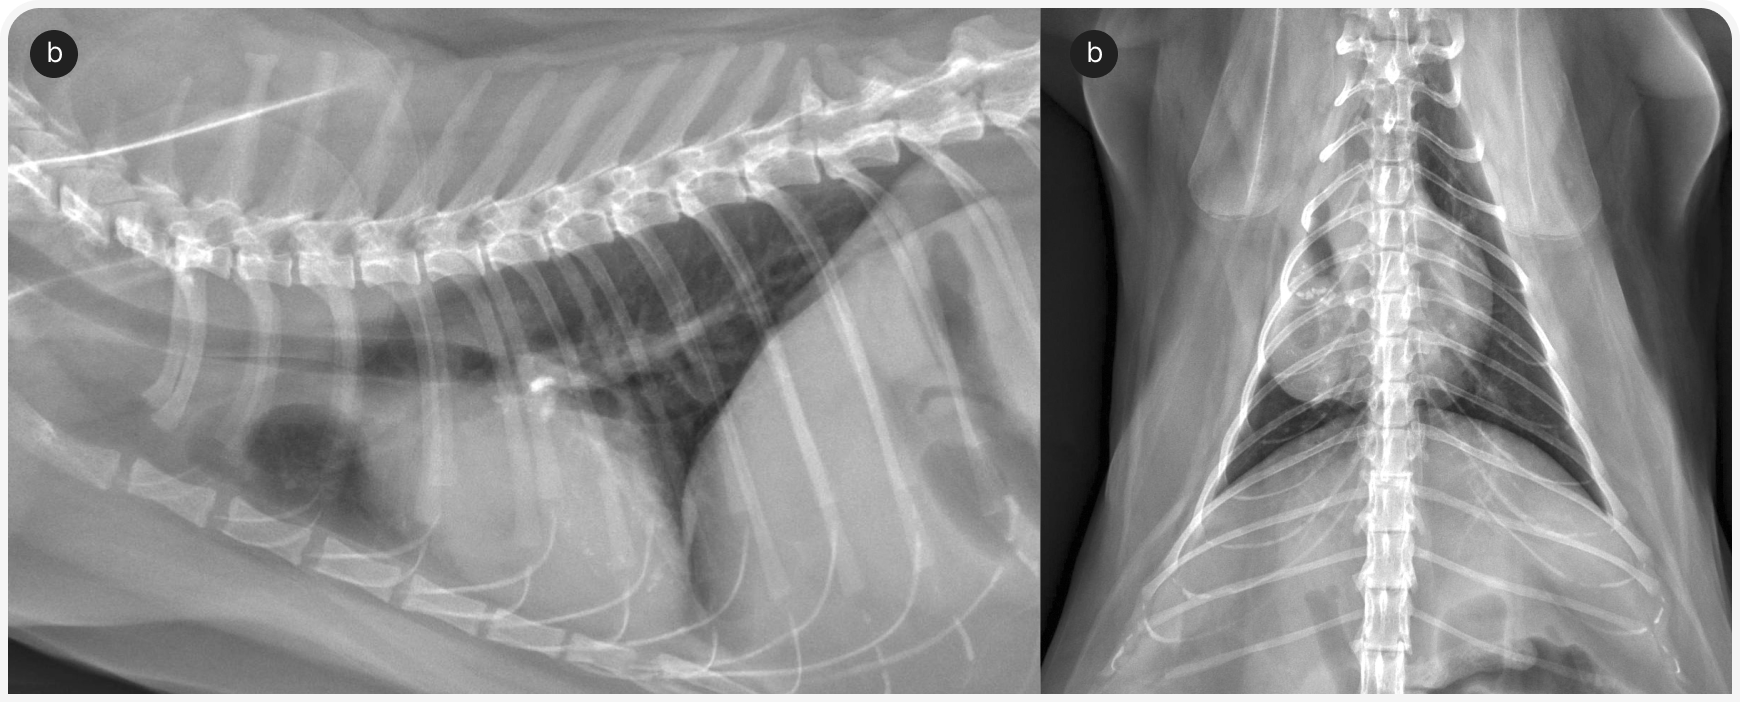

Часто в таких случаях бывает полезно повторить непосредственное обследование, поскольку исходно можно упустить из виду или не принять во внимание незначительные отклонения. Если ранее не определяли балльную оценку мышечной массы, следует сделать это и записать результат. Осмотреть ротовую полость у бодрствующей кошки часто непросто, но значимую патологию можно выявить уже при осмотре зубов и края десен. Однако важно иметь в виду, что беглый визуальный осмотр не позволяет исключить выраженного и клинически значимого заболевания зубов; тяжесть болезненных состояний, таких как резорбция корня зуба, можно определить только рентгенографически (Рисунок 1) (1). Следует провести тщательное офтальмологическое обследование для выявления симптомов увеита или хориоретинита. Эти симптомы неспецифичны, но часто наблюдаются у кошек при грибковых или протозойных инфекциях (Рисунок 2) (2). Нужно тщательно обследовать любые кожные или подкожные узелки, особенно в области внутренних парастернальных лимфоузлов. Также разумно понаблюдать за движениями кошки, чтобы выявить признаки заболеваний суставов, позвоночника или нервной системы; обычно кошек осматривают на столе и поэтому не замечают изменений походки, координации или силы мышц.

При стоматологическом обследовании было подтверждено заболевание пародонта легкой степени и проведено его лечение. При гистопатологическом исследовании биоптатов желудка и двенадцатиперстной кишки была выявлена лимфоплазмоцитарная инфильтрация легкой степени; при биопсии подвздошной кишки и толстой кишки — гистиоцитарная инфильтрация с разрастанием дрожжей в пределах поражения (по внешнему виду, Histoplasma capsulatum).